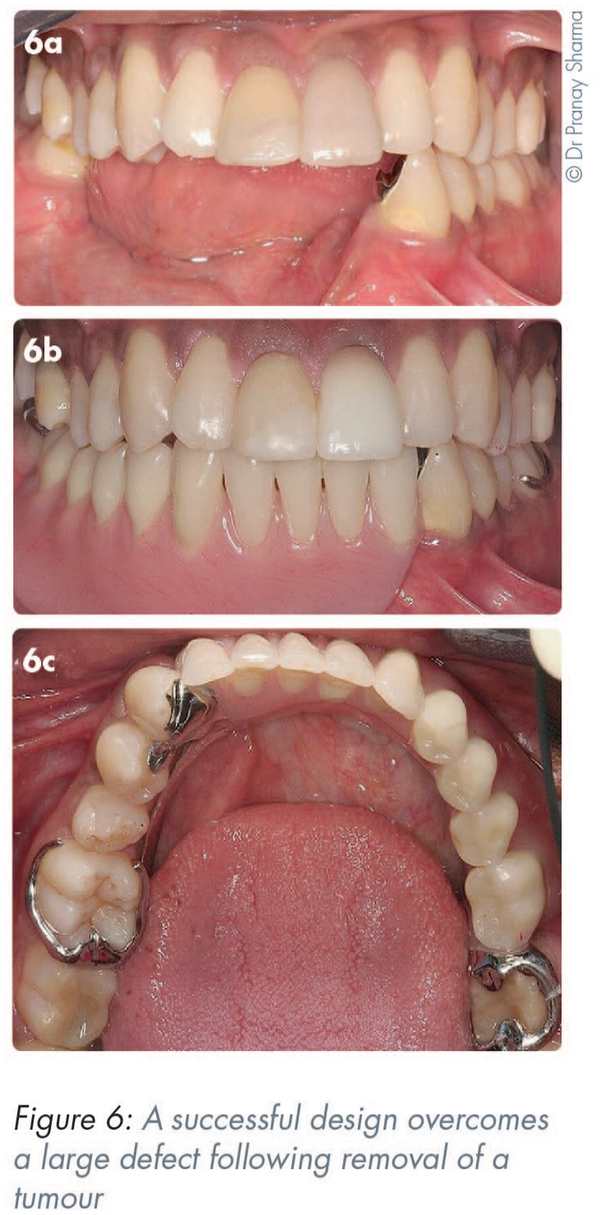

In Figure 6a, the removal of a tumour from the right-hand side has resulted in a large defect. An accurate impression of the teeth and soft tissues is essential. The absence of support for the long edentulous saddle is mitigated by the adhesively secured cast cingulum rest on #33. The shaping of the bulky acrylic base with respect to the tongue and cheek on the right-hand side has maximised retention (Figures 6b-c).

In this example, the cast cingulum rests have been added to abutments adhesively (Figures 14a and 6a). The RPD is designed to engage the cast cingulum rest and thus provide solid aesthetic support to the anterior saddle (Figure 14b).